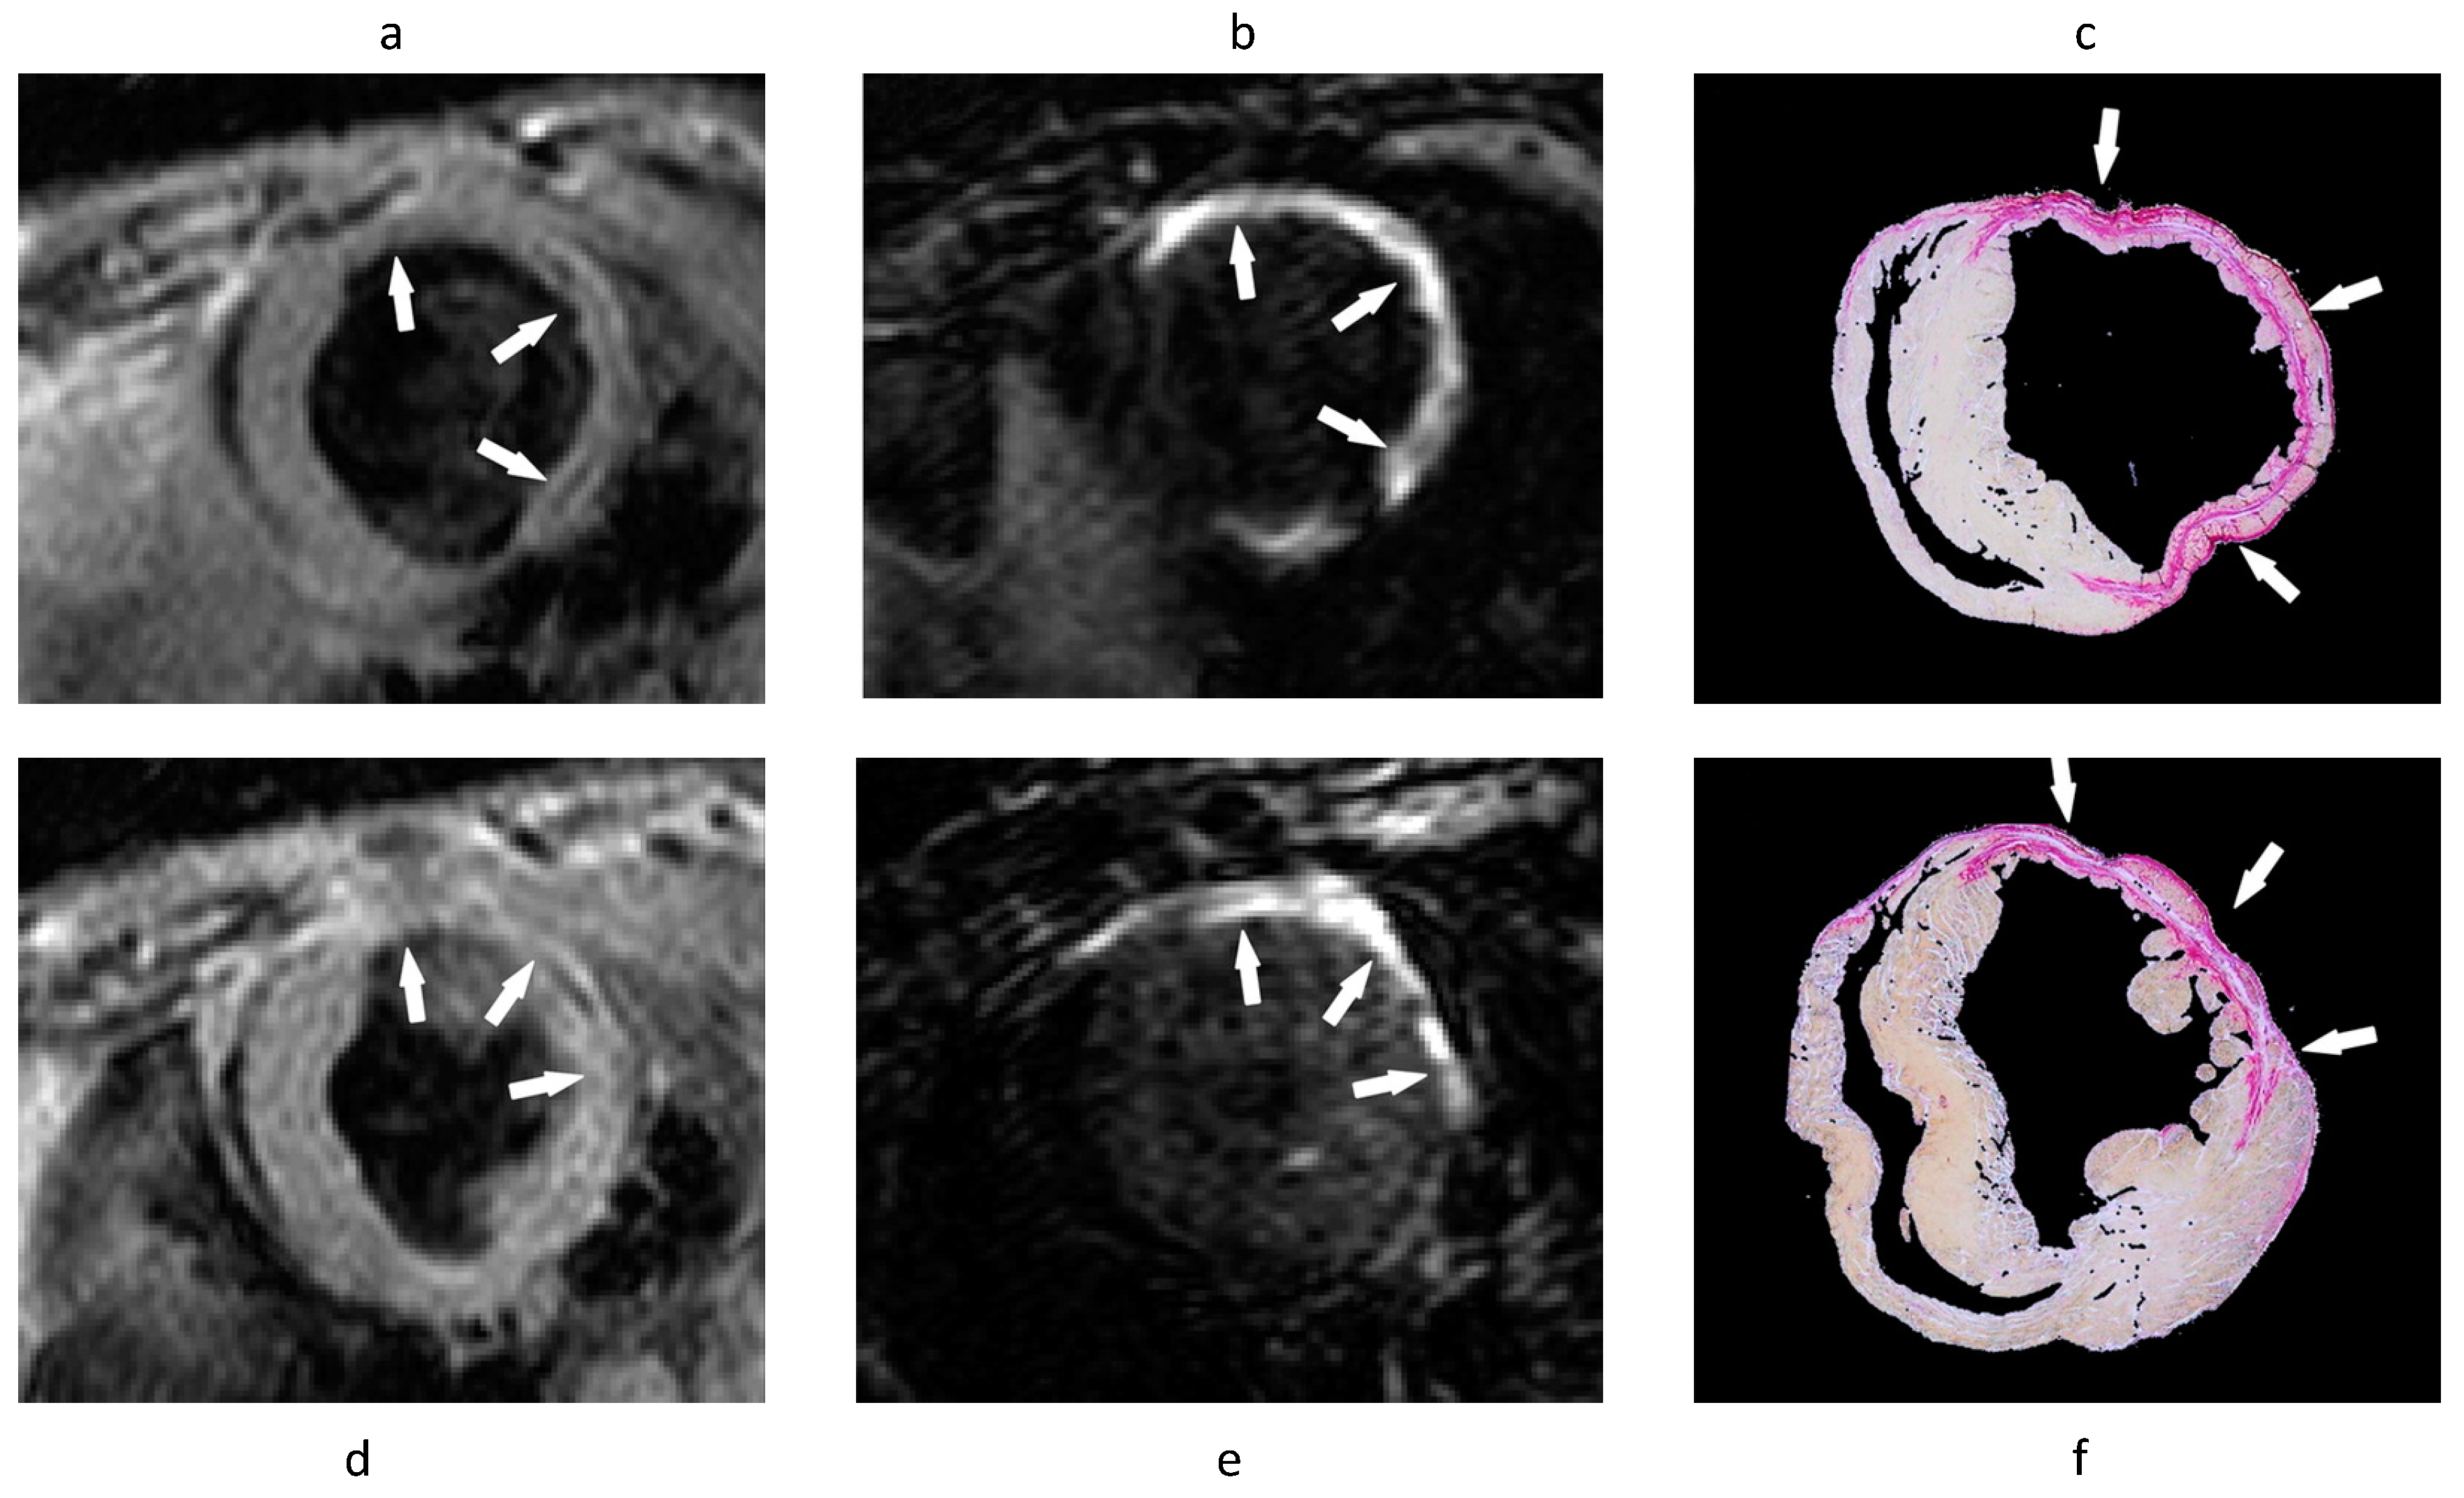

- Wildgruber, M.; Bielicki, I.; Aichler, M.; Kosanke, K.; Feuchtinger, A.; Settles, M.; Onthank, D.C.; Cesati, R.R.; Robinson, S.P.; Huber, A.M.; et al. Assessment of myocardial infarction and postinfarction scar remodeling with an elastin-specific magnetic resonance agent. Circ. Cardiovasc. Imaging 2014, 7, 321–329. [Google Scholar] [CrossRef] [PubMed]

- Protti, A.; Lavin, B.; Dong, X.; Lorrio, S.; Robinson, S.; Onthank, D.; Shah, A.M.; Botnar, R.M. Assessment of Myocardial Remodeling Using an Elastin/Tropoelastin Specific Agent with High Field Magnetic Resonance Imaging (MRI). J. Am. Heart Assoc. 2015, 4, e001851. [Google Scholar] [CrossRef]

- Ramos, I.T.; Henningsson, M.; Nezafat, M.; Lavin, B.; Lorrio, S.; Gebhardt, P.; Protti, A.; Eykyn, T.R.; Andia, M.E.; Flögel, U.; et al. Simultaneous Assessment of Cardiac Inflammation and Extracellular Matrix Remodeling after Myocardial Infarction. Circ. Cardiovasc. Imaging 2018, 11, e007453. [Google Scholar] [CrossRef]